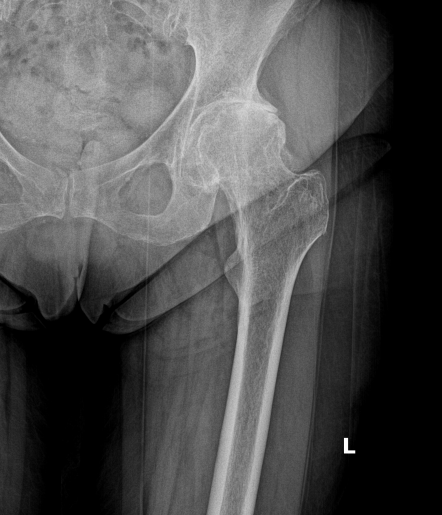

Kalça ekleminde artroz ( aşınma )

Kortizon kullanımına ve alkole bağlı olarak avasküler nekroz dediğimiz femur başında kemik erimesi

Uyluk kemiğinin üst ucundaki bazı kırıklar( femur boyun kırıkları )

Geçirilmiş eklem içi kırıklara bağlı artroz

Doğuştan kalça çıkığına bağlı kısalık ve artroz

Geçirilmiş kalça çıkığına bağlı artroz

Gibi nedenlerle eklem  yüzeylerindeki eklem kıkırdağında ciddi aşınmalar olur. Bu aşınma ileri boyutlara ulaştığı zaman eklemde ağrı ve fonksiyon kaybı olur . Bu durumda kalça protezi operasyonu ile ağrı ve fonksiyon kaybı başarılı bir şekilde tedavi edilebilir.